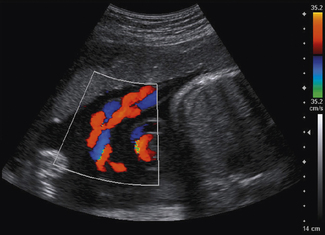

Curvilinear and phased array transducers have a radiating pattern of ultrasound beams that can produce complex color flow images, depending on the orientation of the arteries and veins with respect to the Doppler beam. This can be seen in Figure 11.11 which presents a color flow image of an umbilical cord.

image

Fig. 11.11 Color flow imaging of an umbilical cord highlighting the complex pattern of blood flow